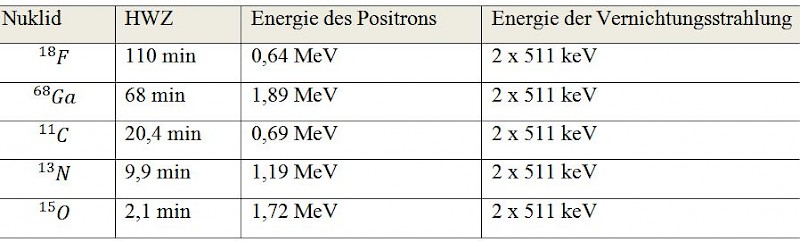

3. Welche Radionuklide bzw. Radiopharmaka werden in der PET verwendet?

Häufig verwendete Nuklide, die für PET verwendet werden, sind:

Das meist verwendete Nuklid in der PET ist der Positronenstrahler F-18. Er wird mit Hilfe eines Zyklotrons hergestellt und kann aufgrund seiner Halbwertszeit von etwa 110 Minuten über etwas weitere Strecken transportiert werden. F-18 kommt aus diesem Grund bei über 90 % aller PET-Untersuchungen zum Einsatz.

Das meist verwendete Nuklid in der PET ist der Positronenstrahler F-18. Er wird mit Hilfe eines Zyklotrons hergestellt und kann aufgrund seiner Halbwertszeit von etwa 110 Minuten über etwas weitere Strecken transportiert werden. F-18 kommt aus diesem Grund bei über 90 % aller PET-Untersuchungen zum Einsatz.- GA-68 gewinnt man mit Hilfe eines Nuklidgenerator aus einer instabilen Muttersubstanz (wie bei dem TC-99m-Generator)

- Die anderen Nuklide können aufgrund der kurzen HWZ, nur in PET-CT-Zentren verwendet werden, die über ein eigenes Zyklotron verfügen.